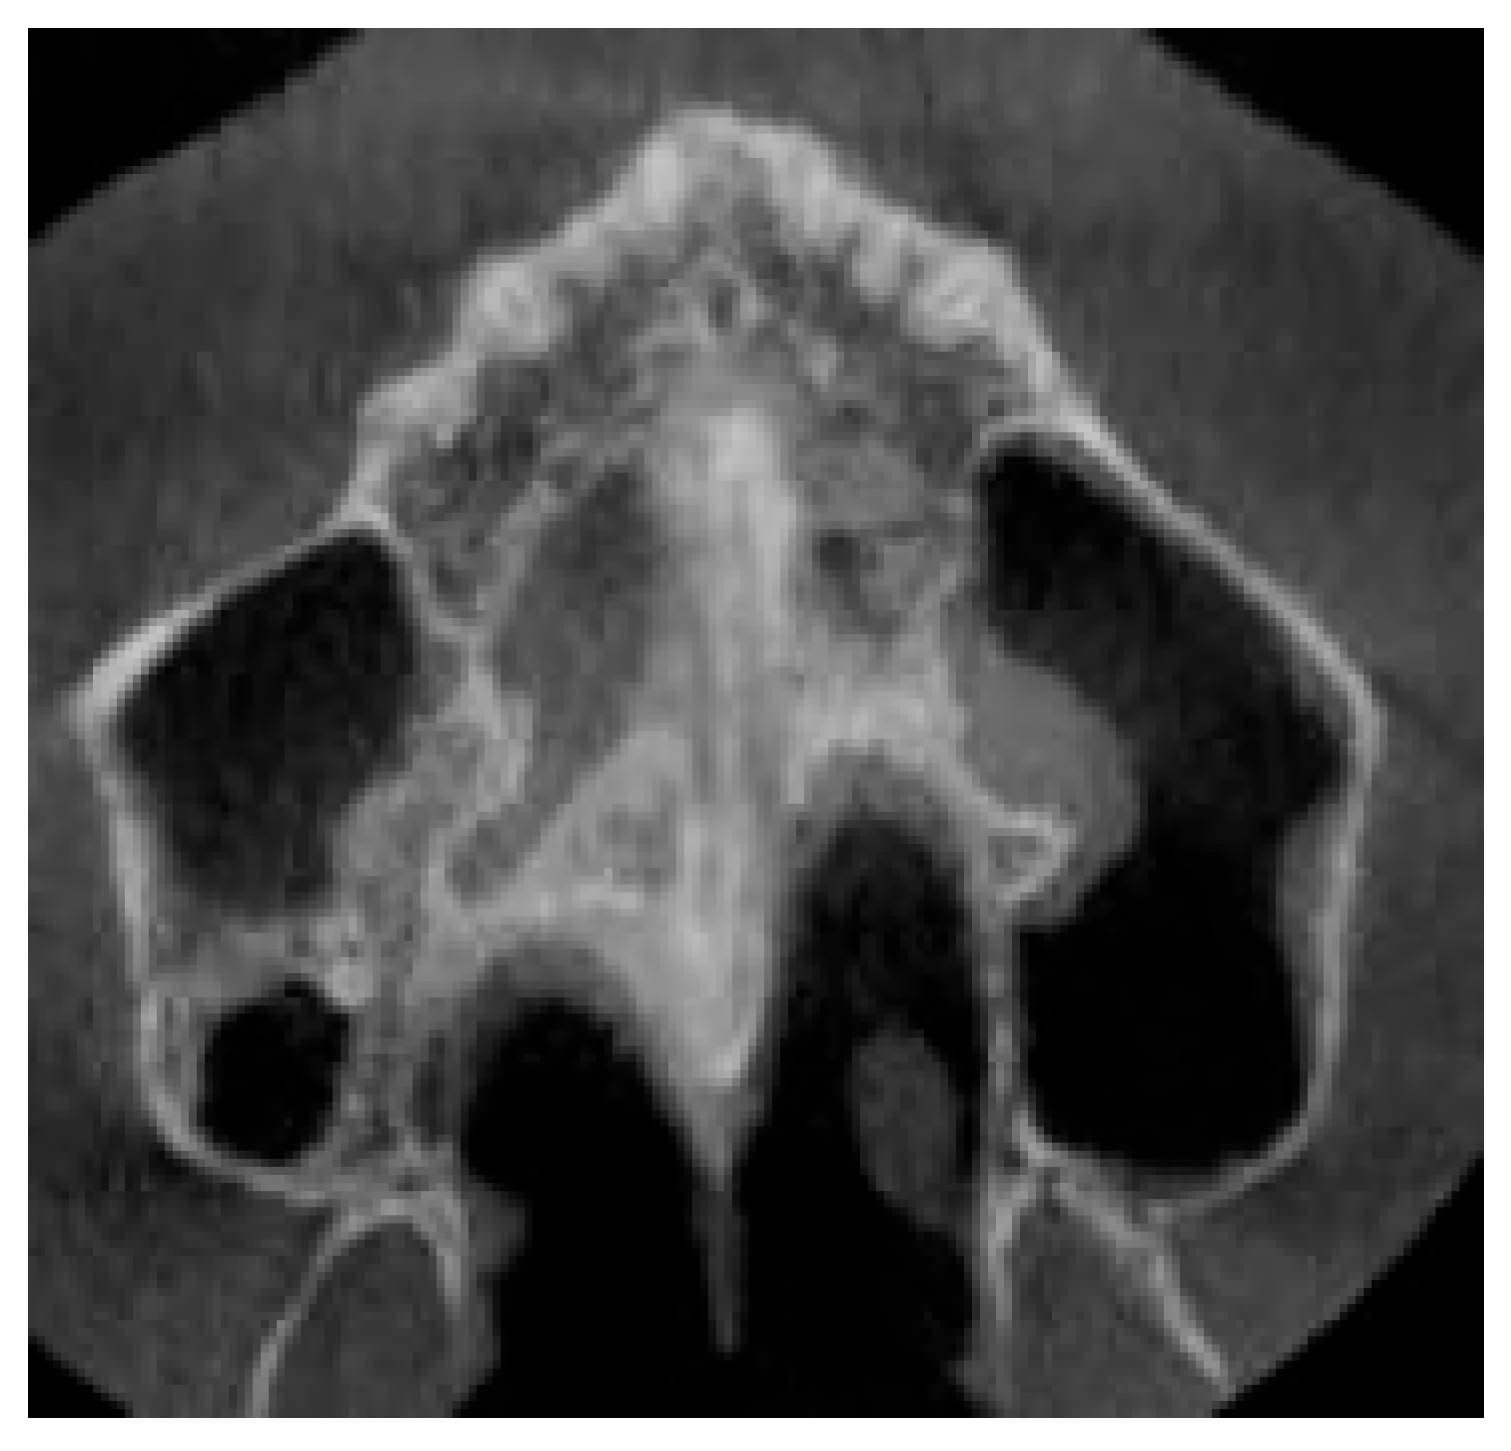

2.9.1. Qualitative Evaluation of Maxillary Expansion on Cone Beam Computed Tomography

3.2. Qualitative Evaluation of Maxillary Expansion on Cone Beam Computed Tomography

3.3. Quantitative Two-Dimensional Analysis of Upper Palatal Expansion on CBCT